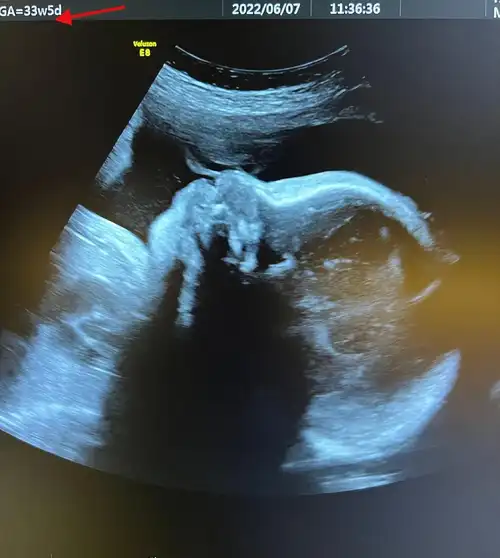

宝妈:男孩还是女孩?不妨看b超单上的这3个数据,准确率极高!

在孕晚期的时候,如果b超单上出现肾盂分离,可能一般是男孩,如果b超单

陈燃预产期将至,晒b超照曝二胎是男孩,提前公布宝宝性别惹争议

孕晚期,若b超单上经常出现这"5个字"家里可能要添"男丁"恭喜_检查